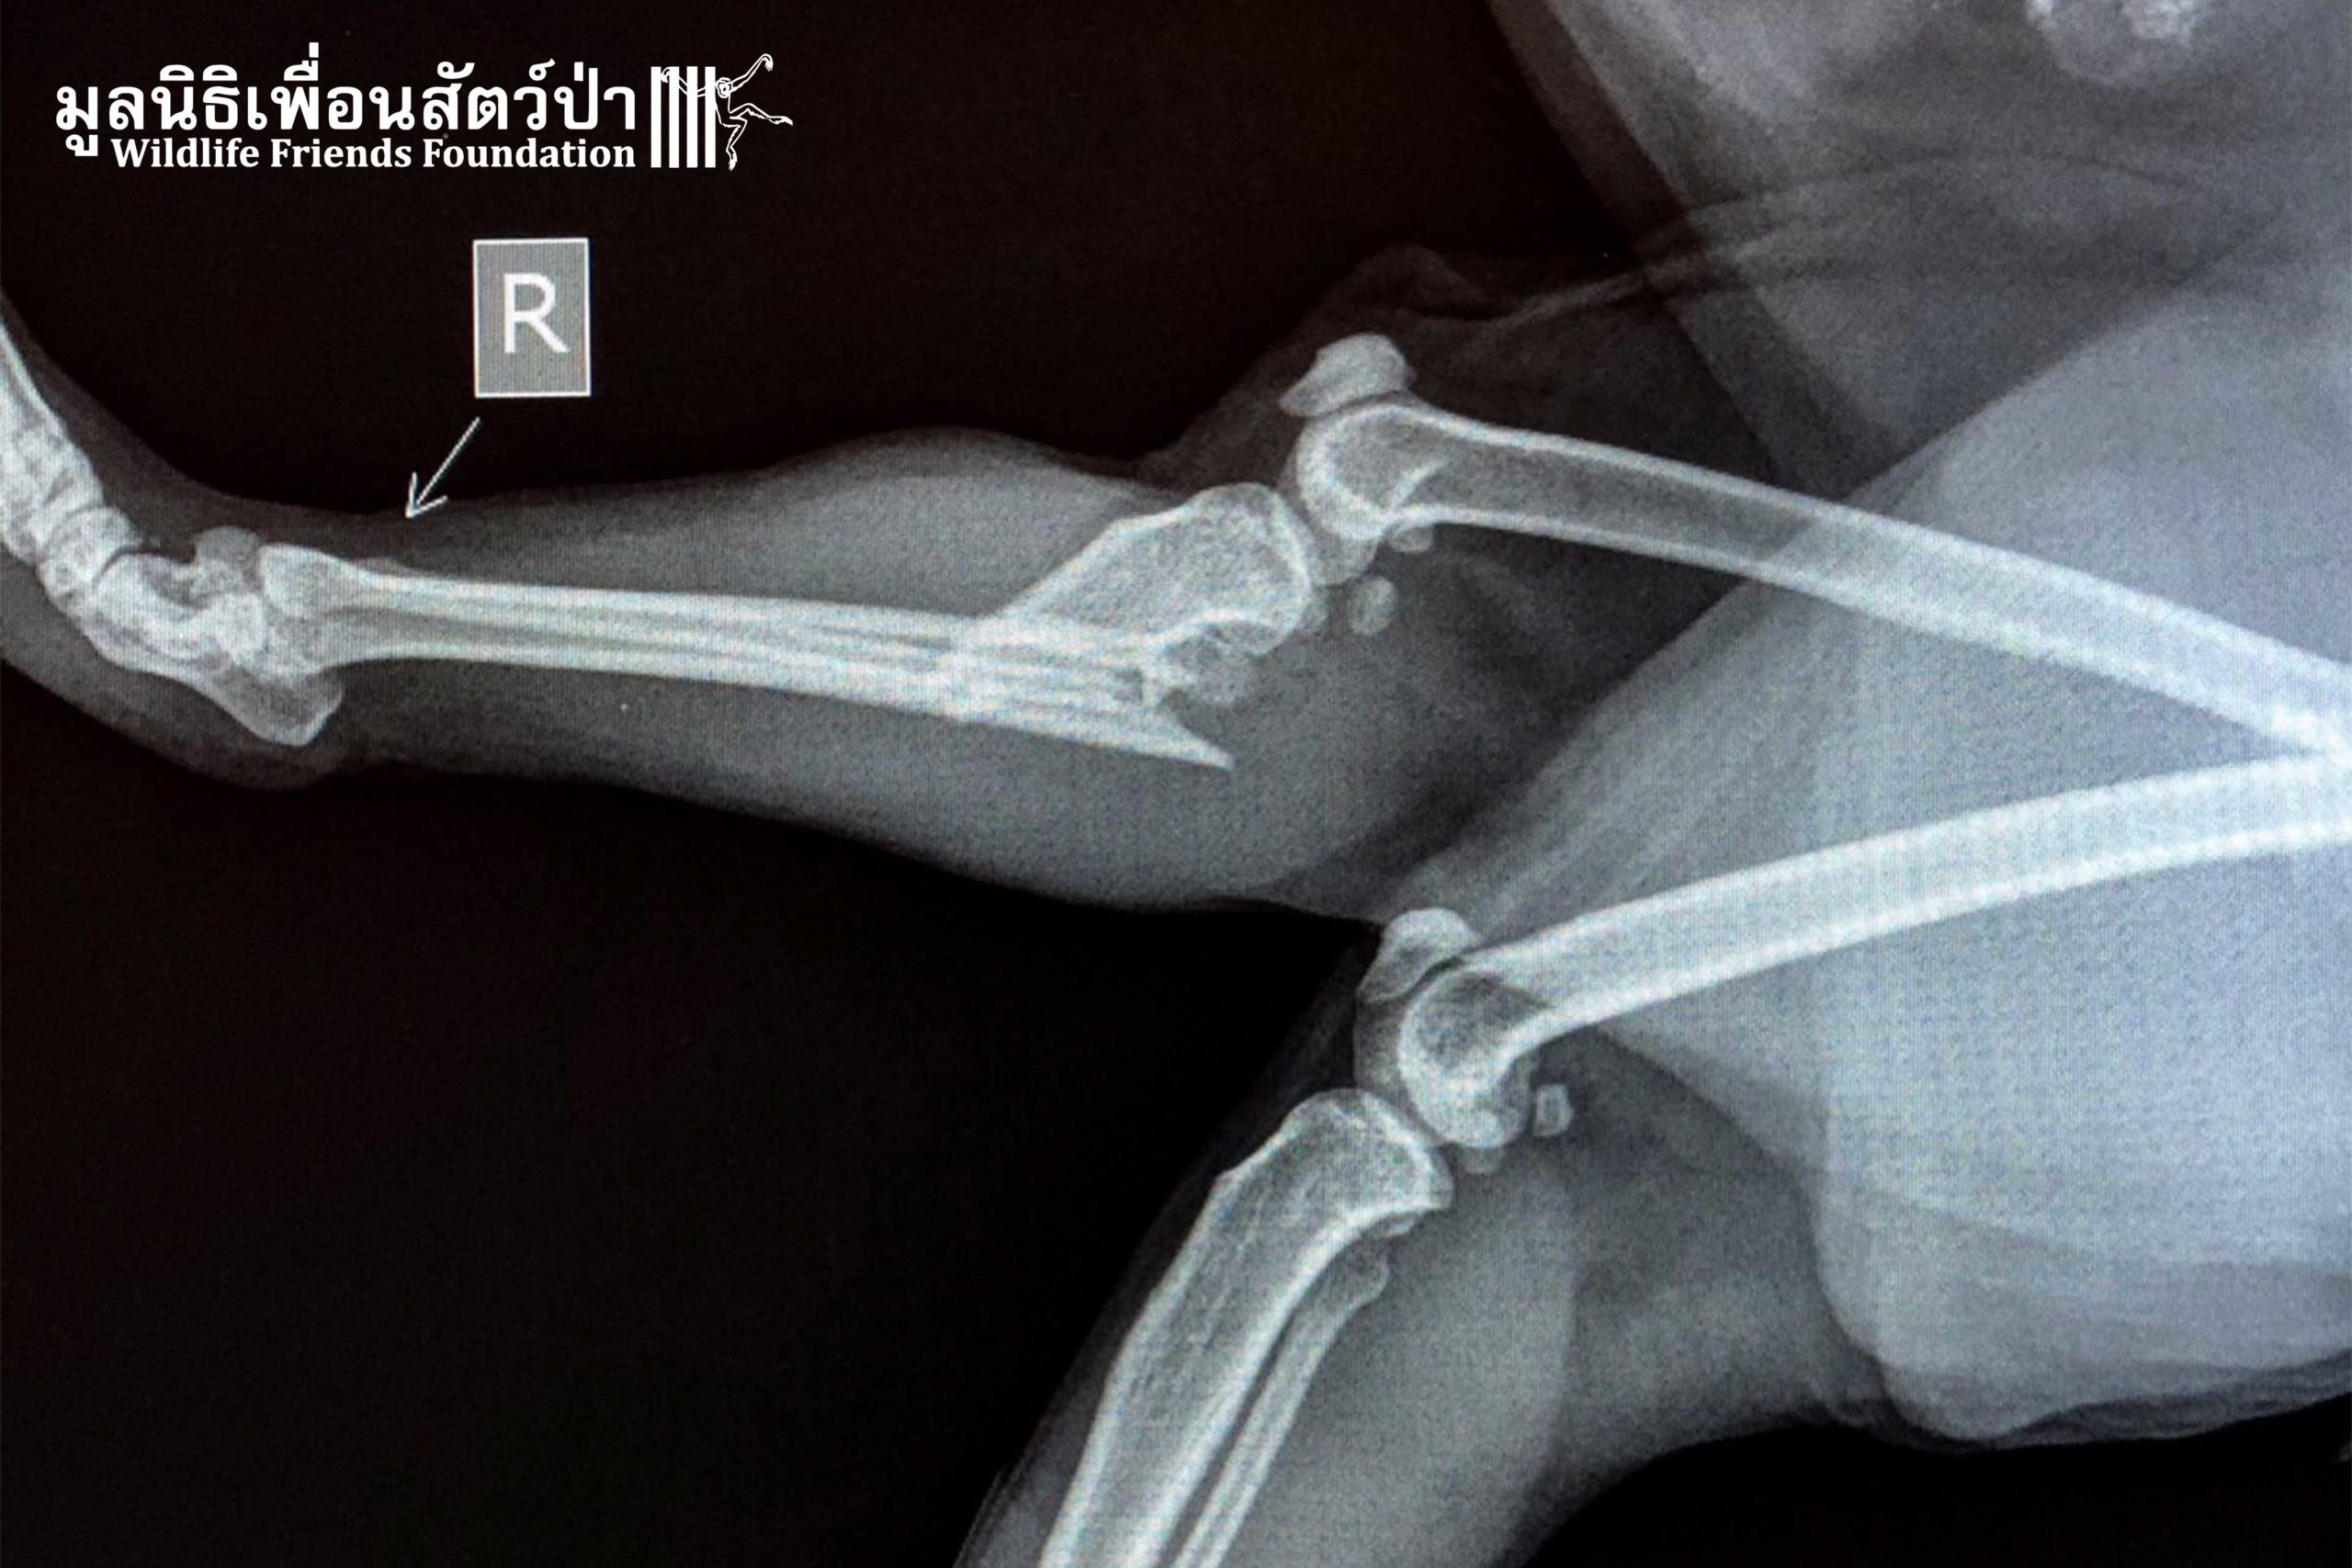

Susan arrived at WFFT, the Vet Team took her straight to an X-ray. It was found that she has broken left collarbone and a broken right leg. She also has wounds on her head and tail.

The Vet Team fitted a cast on her leg, cleaned her wounds, and let her take a rest in the hospital. You can tell by her face she must be in real pain but don’t worry she is now in good hands. She will receive all the necessities that she needs until she can get back on her feet again. We are hooping she can recover from this terrible ordeal. Get well soon, Susan!